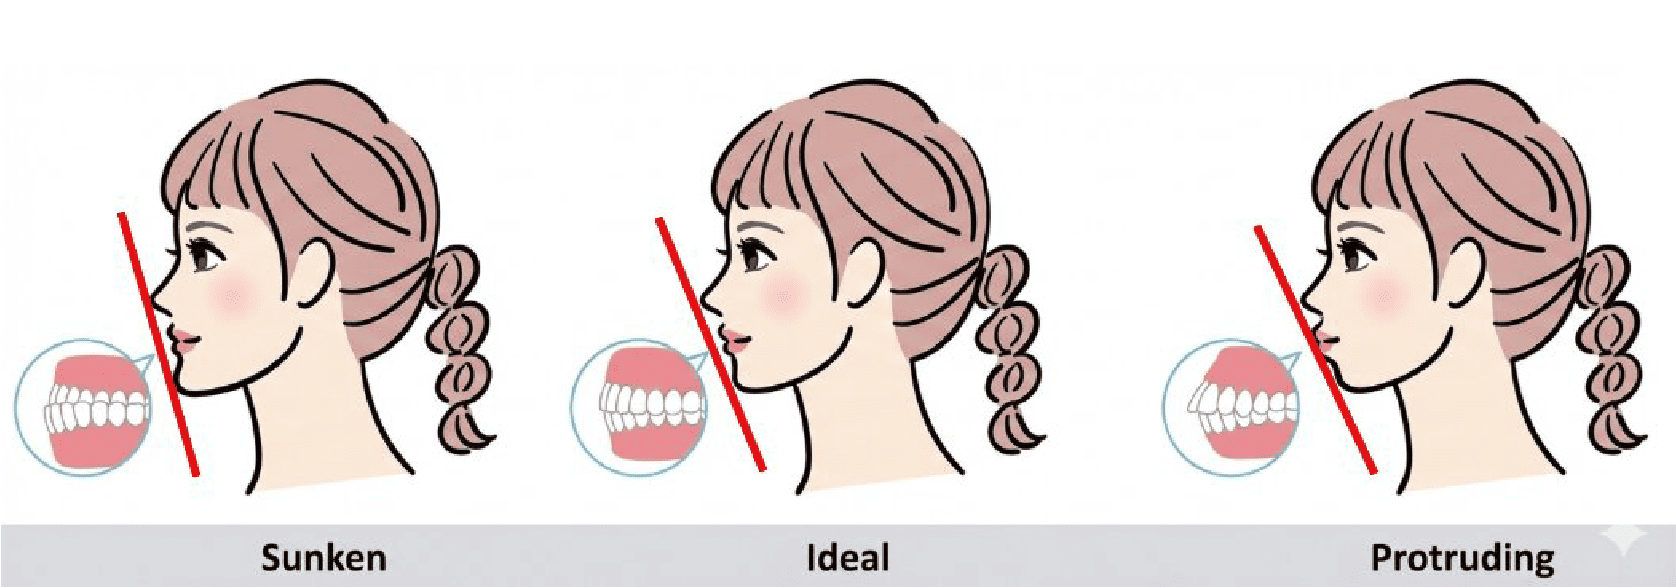

Dental Condition: Protruded side profile

(Facial Profile Analysis)

Unlike metal braces that often rely on extraction to create space, clear aligners allow gentle arch expansion and digitally planned movement (distalization etc) to ensure the least compromise in facial profile.

Perfect if your facial profile makes you unsuitable for extraction.